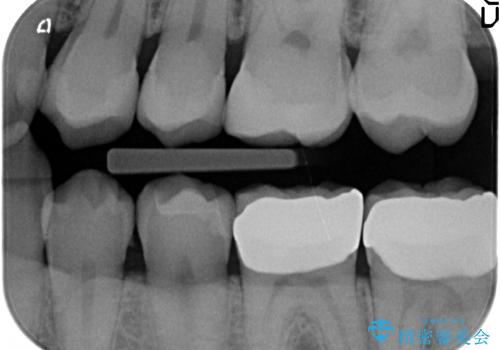

放置した虫歯の治療 親知らずの手前が虫歯

- 詰め物が取れて放置していたとのこと。

虫歯が大きかったため、被せ物(クラウン)としました。

親知らずを抜いてから治療しています。

- 22万円 (左下67 仮歯1万円x2 ジルコニアクラウン10万円x2)費用は治療当時の料金となります

幸い神経を取らずにすみました。